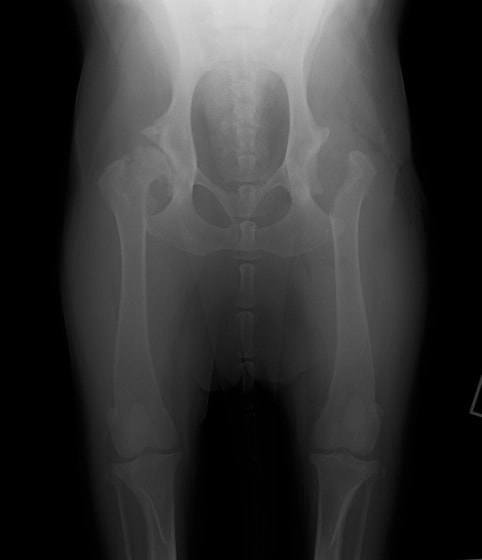

レッグぺルテス罹患症例の股関節のレントゲン写真

レッグペルテス病/無菌性大腿骨頭壊死症はトイ種やテリア種などの小型犬に好発し、5~8ヶ月齢の若齢期に多く発症します。大腿骨の先端(大腿骨頭)が、血液供給の障害により成長が阻害され、大腿骨頭の変形や壊死を起こす病気です。罹患動物は股関節の強い痛みのため、日常生活においては進行性の跛行(ケンケンをして歩く、足を地面に着かない等)の症状が認められます。肢を使わなくなるため筋肉量は減少し後肢は細くなります。

診断方法は主に触診と画像検査により行われます。触診では足を後方に伸ばし、疼痛の有無を調べます。レントゲン検査では、大腿骨頭や骨頸の骨密度の低下、大腿骨頭の辺縁部の変形、大腿骨頭や骨頸の亜脱臼等が認められることがあります。しかし発症初期では、レントゲン所見には異常が認められず、繰り返しのレントゲン撮影、CT検査を行う場合があります。